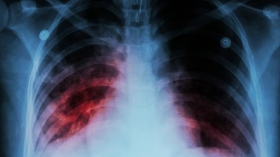

Врачи рассказали «Суспільне.Миколаїв», что люди, болеющие туберкулезом, могут не волноваться насчет заболевания COVID-19, потому что они не попадают в группу риска по природным причинам.

Директор Николаевского регионального фтизиопульмонологичного центра Ольга Пархоменко успоила пациентов с туберкулезом, которые опасались заражения коронавирусом.

— Любой человек, который имеет пониженный иммунитет — это «группа риска», но сказать, что больные туберкулезом чаще болеют, я бы так не сказала. Больше «группа риска» — это пациенты, все же, с сахарным диабетом, с сердечно-сосудистыми заболеваниями, — рассказала Ольга Пархоменко.

При этом в начале оба заболевания протекают по схожим симптомам, так что заболевший может перепутать: кашель, отдышка, скачки температуры, в некоторых случаях, кашель с кровью.

Медик считает, что пандемия коронавируса может привести к непредвиденному росту случаев заболевания туберкулезом, так как его тяжелей диагностировать.

Ранее сообщалось, что в Николаевской области насчитывается около 1200 активных больных туберкулезом, из них 13 - дети.